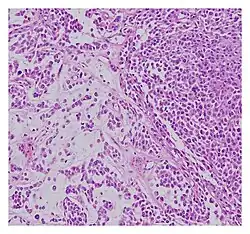

Histopathological examination of malignant chondroid syringoma

Histologically, these malignant mixed tumours have epithelial and mesenchymal components and are very large, nodular, circumscribed, and nonulcerated.[11] They are morphologically identical to pleomorphic adenoma and have a female predilection.[4] They range from developing deep dermal to subcutaneous nodules and metastasise at a very high rate.[4][8] Malignant mixed tumours can emerge "de nova or more rarely develop from a cartilaginous syringoma."(IADVL, 2004)[11]